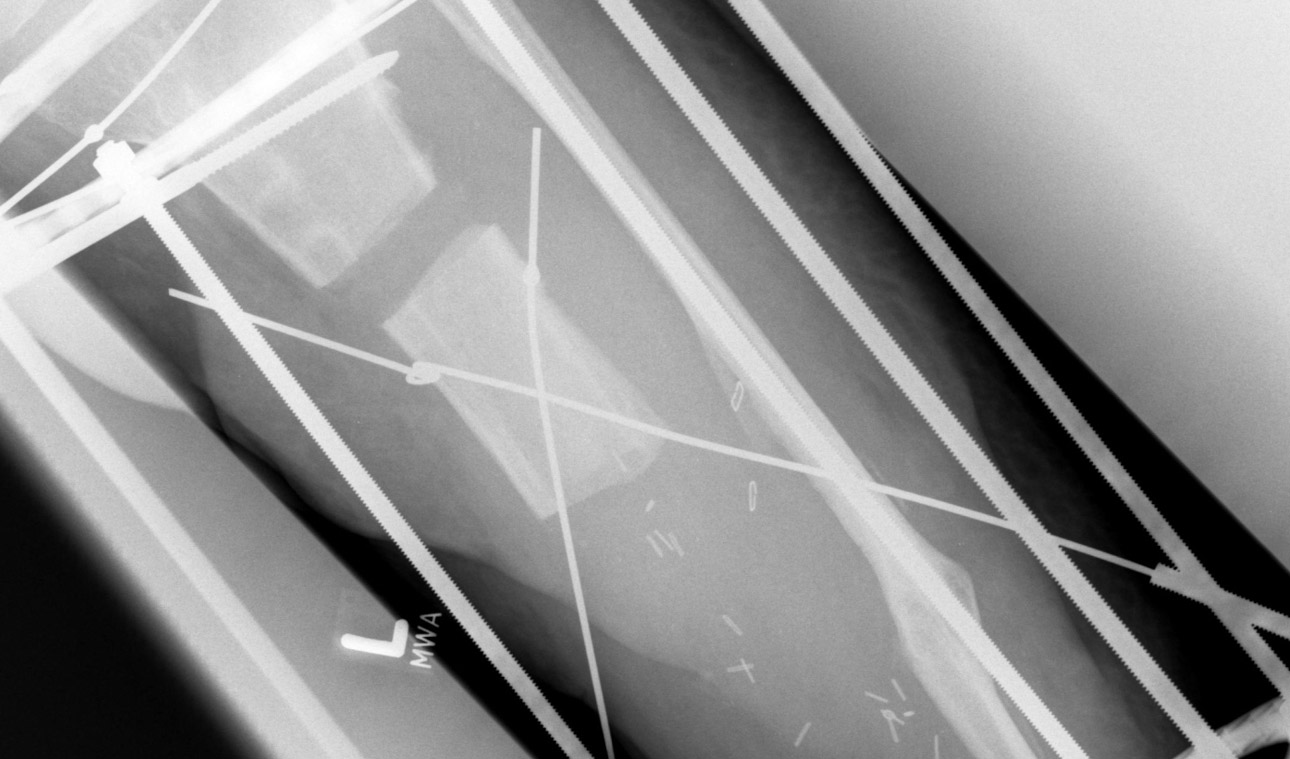

In der modernen Unfallchirurgie werden zunehmend schonendere (minimalinvasive) Verfahren zur Stabilisierung selbst großer Röhrenknochen und der Wirbelsäule entwickelt, um für den Patienten die zusätzliche Belastung durch die Operation möglichst gering zu halten....